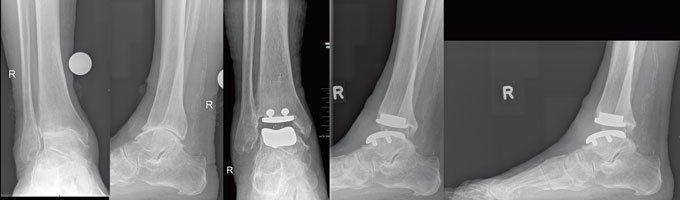

„Das Röntgenbild zeigt meist eine Verengung des Gelenkspalts und charakteristische Knochenveränderungen im betroffenen Gelenk.“ Mit der Kernspintomografie lassen sich auch Knorpelveränderungen darstellen. Typische Veränderungen der Laborwerte gibt es bei einer Arthrose nicht. Eine Blutuntersuchung kann aber zeigen, ob sich die Arthrose in einer aktiven Phase befindet und sie dient auch dem Ausschluss anderer Gelenkerkrankungen wie Rheuma oder Gicht. „Und in manchen Fällen gibt es Fehlstellungen wie X- und O-Beine, die eine Arthrose-Bildung begünstigen können.

Oftmals hilft auch hier eine operative Korrektur, Arthrose vorzubeugen“, erklärt Dr. von Foerster. „Vor solch einer Operation schrecken viele Menschen erst einmal zurück“, weiß der erfahrene Mediziner aus seiner Sprechstunde. „Doch in der Hand eines erfahrenen Chirurgen, und hier ist die Anzahl der von ihm durchgeführten Gelenkersatzoperationen maßgeblich, sind die Aussichten auf Erfolg sehr gut.“ Häufig betrifft die Arthrose auch das obere Sprunggelenk. Entzündungszeichen am Gelenk sind typische Hinweise auf eine Arthrose im Sprunggelenk. „Heute ist es möglich, dieses Gelenk mit einer Endoprothese zu versorgen“, so Dr. von Foerster. „Auch diese Operationstechnik wird mit sehr gutem Erfolg durchgeführt.“ Die Ärzte der ENDO-Klinik Hamburg haben bislang mehr als 143.000 Kunstgelenke eingesetzt. Sie ist damit die führende Klinik in der Versorgung von Hüft-, Knie- und Schultergelenken und feiert in diesem Jahr ihr 40-jähriges Bestehen. Nach einem zweiwöchigen Krankenhausaufenthalt beginnt in der Regel dann ein physiotherapeutisches Training, damit die Muskeln wieder aufgebaut und der Umgang mit dem Kunstgelenk erlernt werden kann. Das neue Gelenk ist, je nach Beanspruchung, 20 Jahre oder länger haltbar. Danach kann es ohne Probleme ersetzt werden.